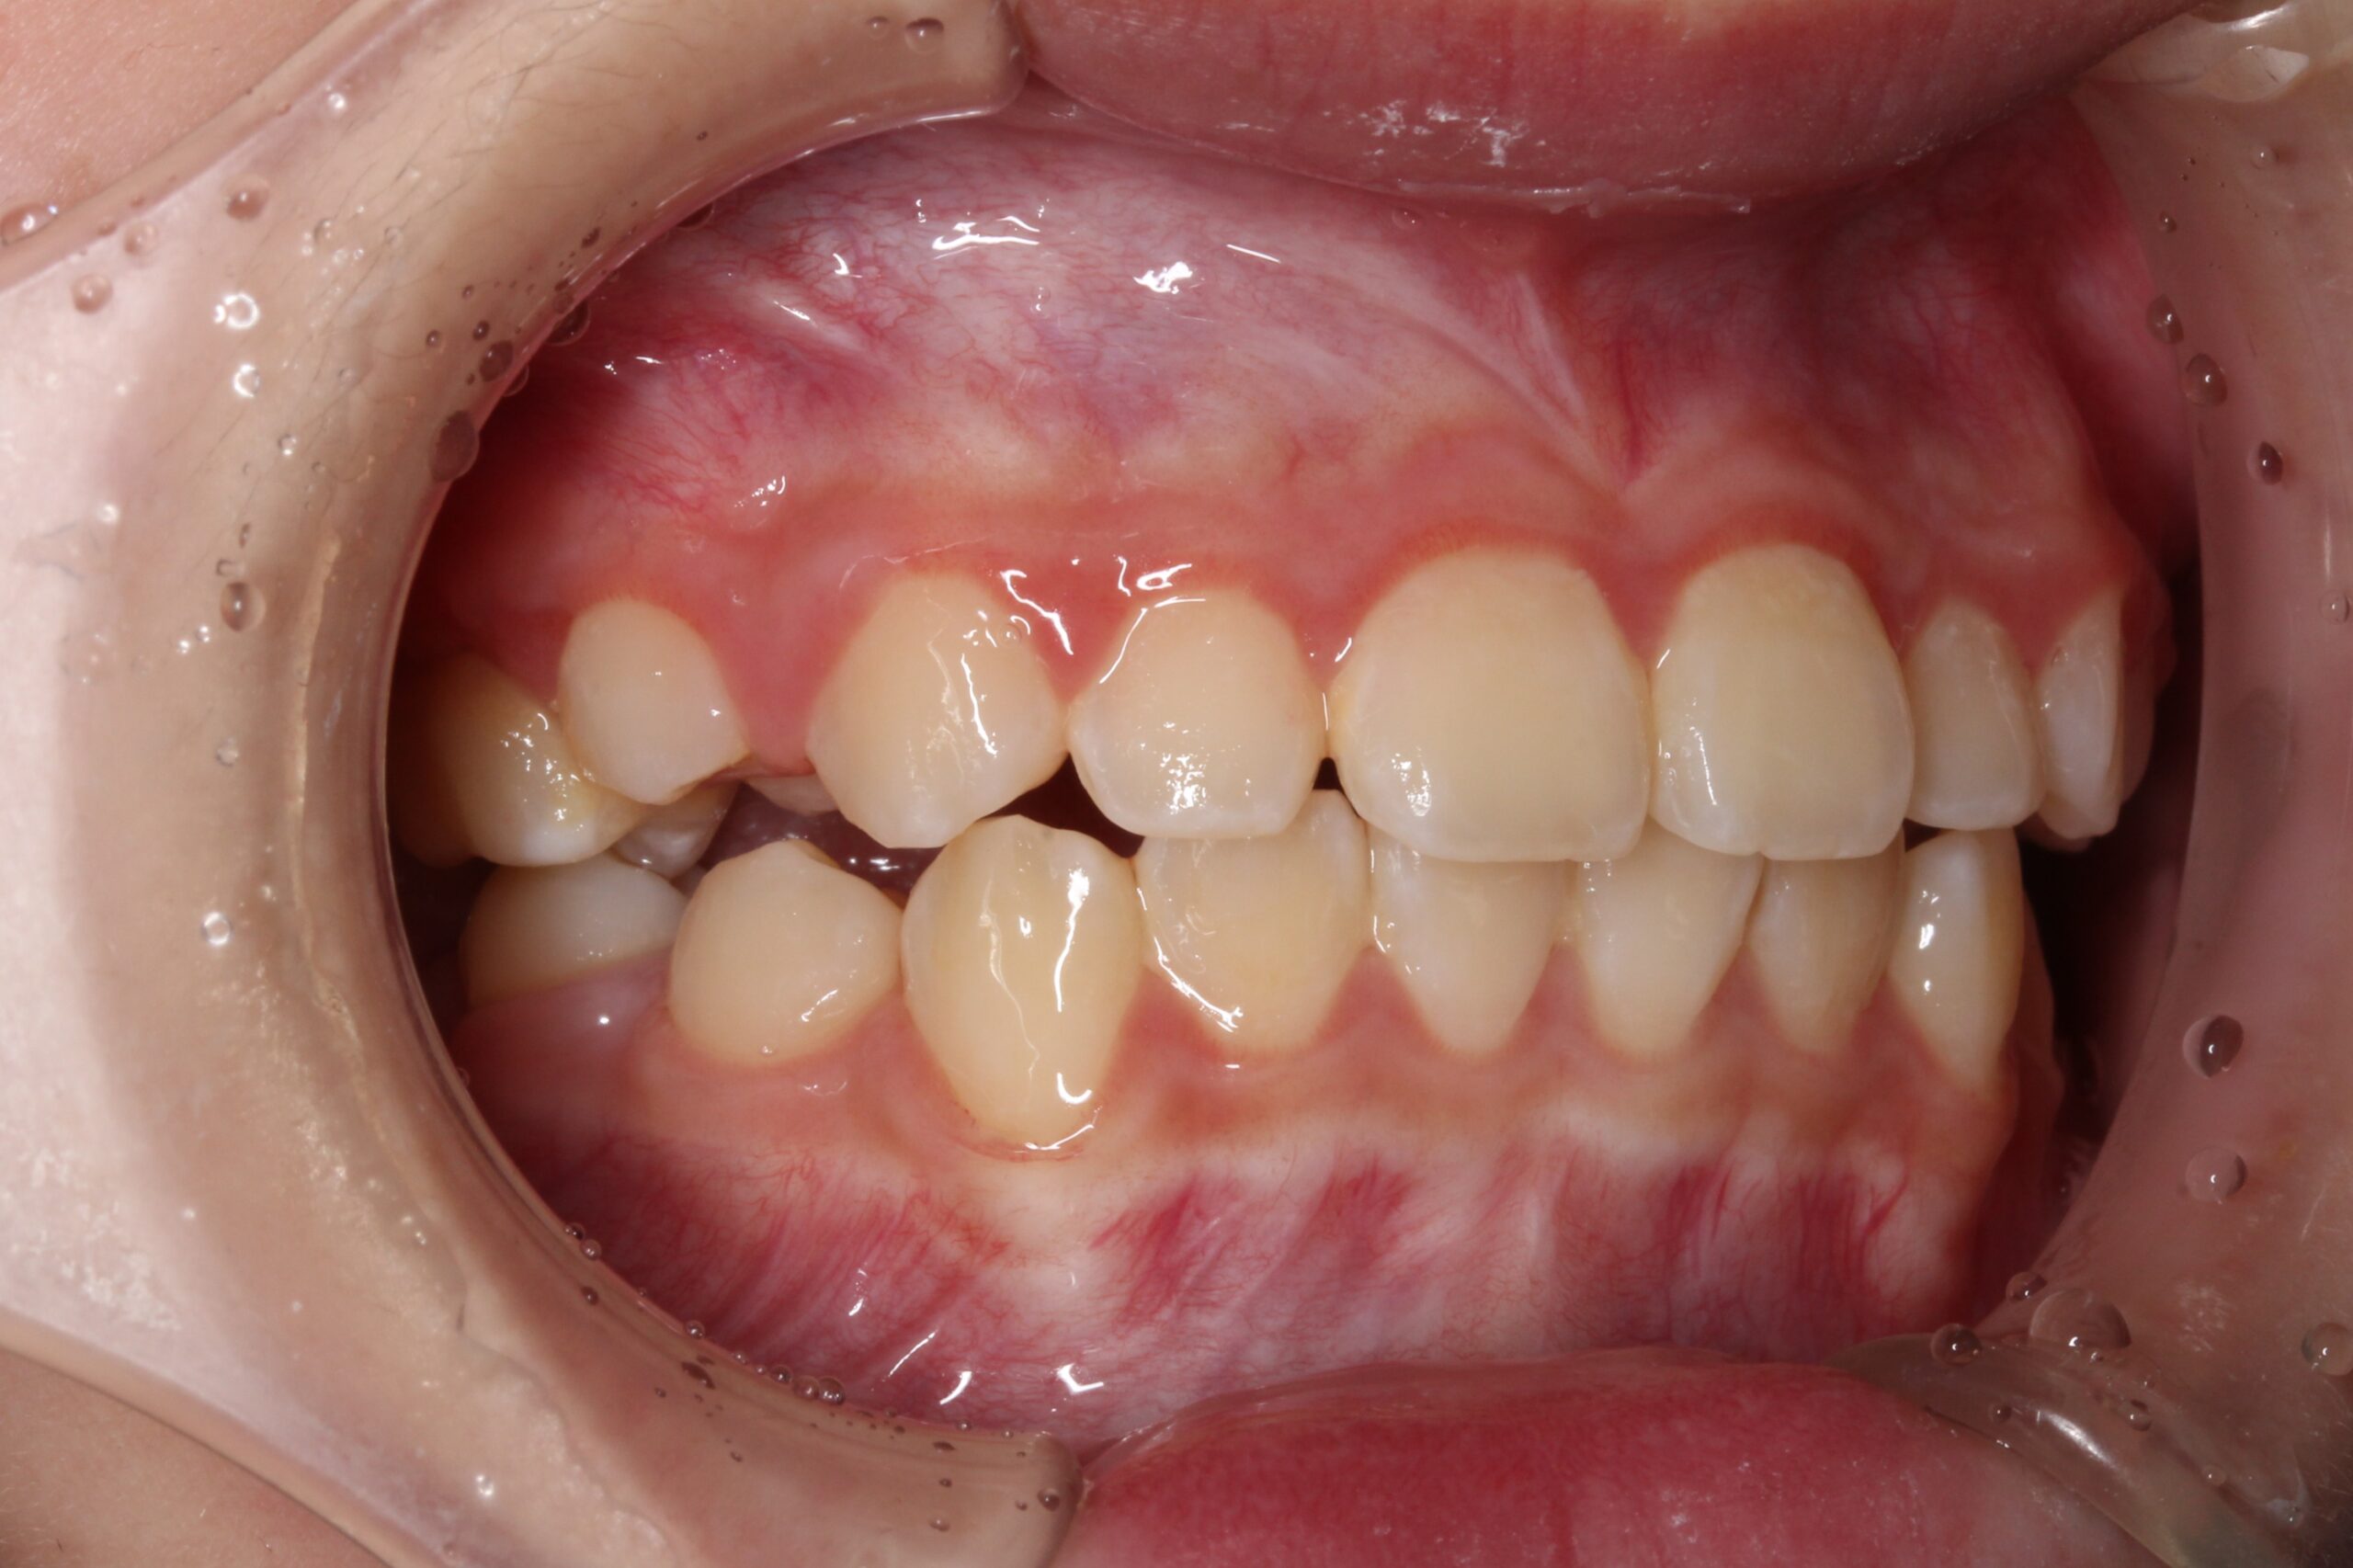

矯正術後:右側

| 治療期間 | ・マウスピース矯正:10カ月 |

| 治療費用 | 770,000円(税込) |

| 治療内容 | 患者様は全体的な歯並びのがたつきを気にされており、矯正検査後叢生Ⅰ級と診断いたしました。 |

| リスク・副作用 | ・着脱式の装置を使用して抜歯をせずに歯が並ぶように小学生の間にスペースを確保します。着脱式装置のため指示通り使用しなかった場合はいい結果が得られません。保護者による装着時間の管理は必ず必要です。 ・ご予約された日にご来院が3回なかった場合、矯正治療中に虫歯予防をすることなく虫歯が多発する場合は治療中止を含めた話し合いの機会を設けます。 ・装置が変形、紛失、破損した場合はLINEにてご連絡ください。 ・治療後は矯正治療で動いた歯が元に戻らないように装置で保定する期間が必要です。保定装置装着を怠るなどの理由で歯並びが崩れた場合は治療開始から1年6か月以内の場合に限り割引費用(110,000円)で追加マウスピース矯正を一度だけ対応します。※1年6か月以降は正規のマウスピース矯正費用(440,000円〜)がかかります。 ・保定装置は2〜3年で変形・破損の可能性があるため、定期的に作り直しが必要です。保定装置の破損や生え変わりにより合わなくなったときは有償で製作させていただきます。 ・成長期に行う矯正治療は完全な成長予測はできません。予想外の成長によっては治療計画が変更になることがあります。 ・永久歯が自然に生えてこない、生える方向が著しく悪い、埋まったまま生えてこない(埋伏歯)の場合はブラケットによる追加矯正が必要になります。(追加費用が必要です) |